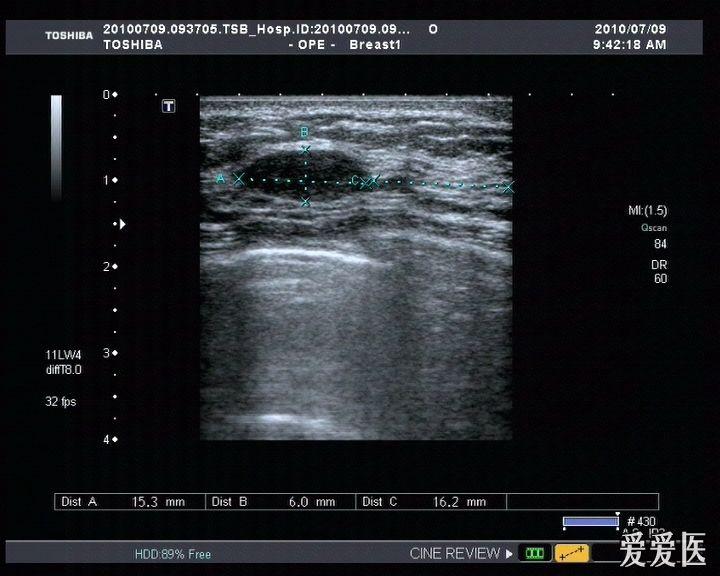

乳腺纤维腺瘤

图片尺寸960x720